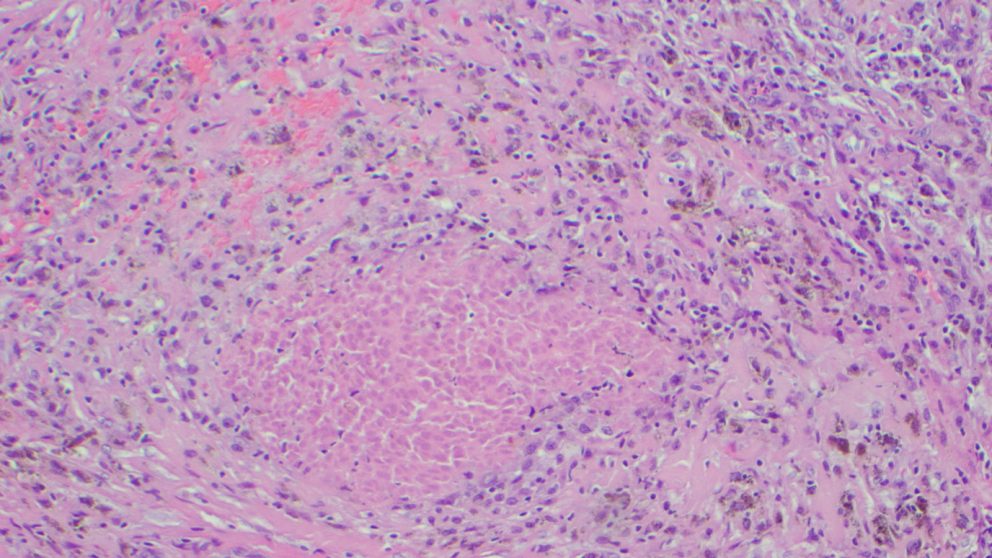

Because of the strong association to outcomes with major pathologic response, researchers evaluated biomarkers to better understand the factors associated with treatment response.

They found that patients who had high pre-treatment levels of one biomarker, called TIGIT, or low levels of another biomarker, called B7-H3, had the best chance of remaining recurrence-free, highlighting the potential to use these markers to predict patient responses in the future.